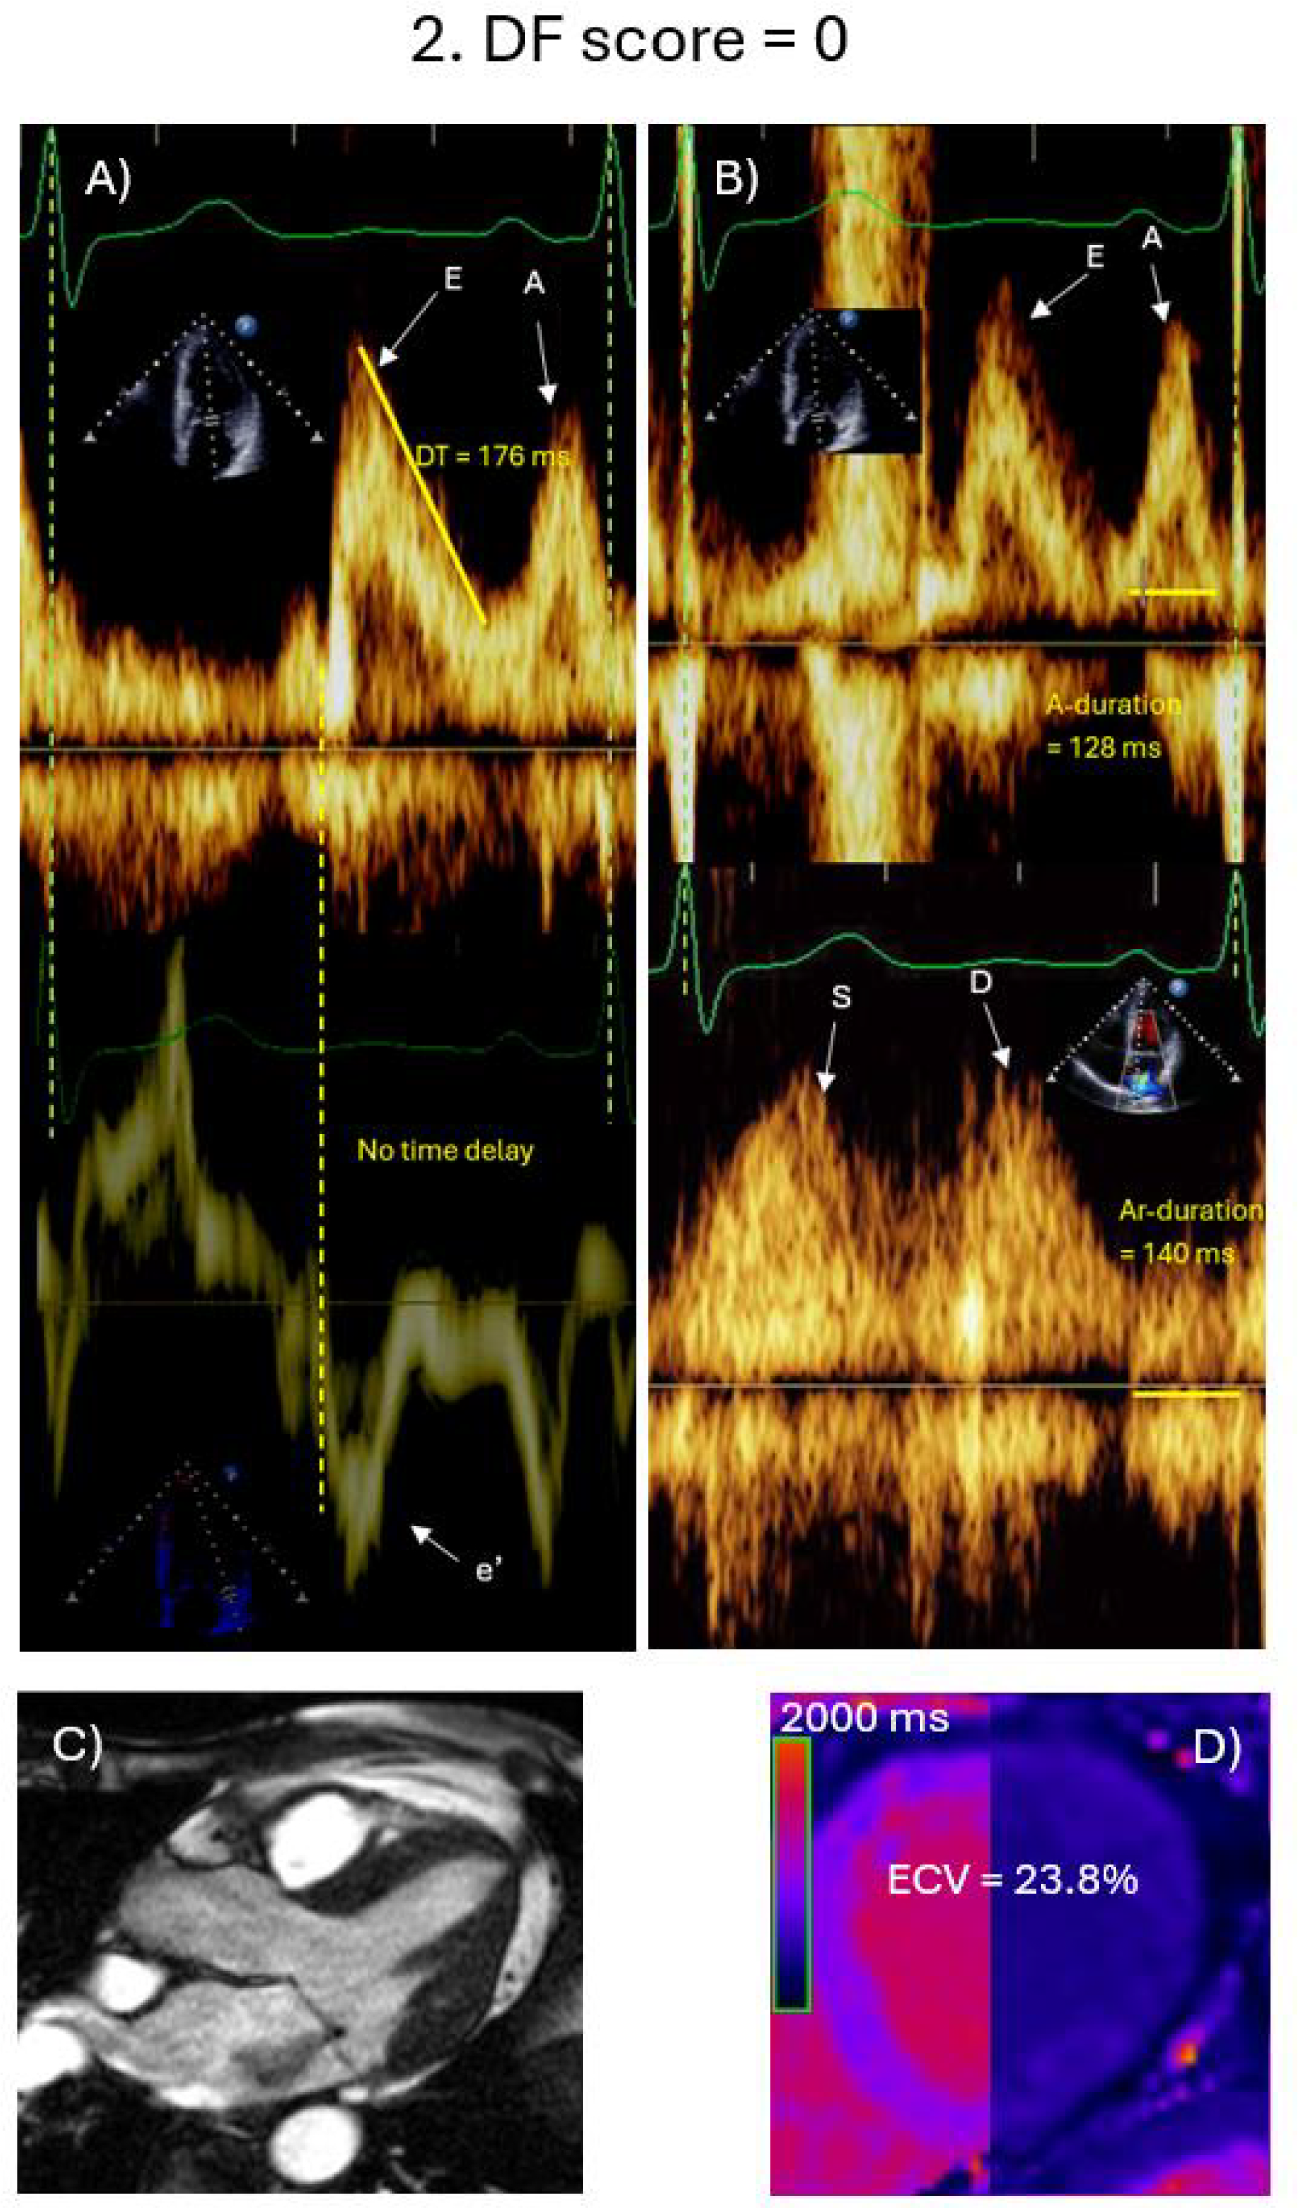

Fig. 1

Echocardiographic and CMR findings in a 66-year-old female with primary MR and normal diastolic function. The Echocardiogram shows early mitral velocity (E) of 100.0 cm/s, late mitral velocity (A) of 83.2 cm/s, and E/A ratio of 1.2. No time delay is present between onset of E velocity and onset of mitral annulus septal e’ velocity. Deceleration time is 176 ms (A). Mitral A-duration is 128 ms, while pulmonary vein atrial flow (Ar) duration is 140 ms and Ar-A = 12 ms (B). By CMR (1.5 T), the MR jet is visualized in the horizontal long axis view (C). Pre-contrast T1 map is shown (D), and ECV is 23.8%. The patient was followed up for 137 months with no events.